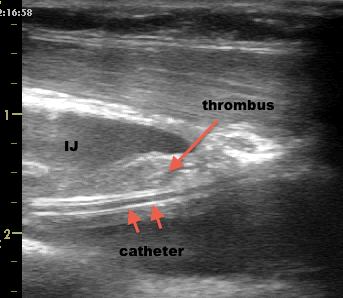

2. I have been teaching bedside ultrasound for the last 5 years, and practicing it for over a decade. I teach ultrasound-guided line workshops. The ability to safely and properly follow a needle tip to venous puncture is an expert-level skill. I cannot count how many times a participant has sworn that his beam is right at the tip of the needle and been befuddled when I point to the blue phantom and show him how he is scanning just a bit beyond the hub and that the tip is in fact several centimetres into the blue phantom (better the phantom than the lung!). The problem comes from a false sense of confidence and security that the procedure being “guided” provides. I’ve already seen several carotid insertions and pneumothoraces with IJ and SC guided procedures…

So…what is my preference? I spot all lines, meaning that I scan both sides of the neck for jugular size, position relative to the carotid and anomalies. I then do the IJ line blind, unless it is particularly small or really anomalous (eg right on top of the carotid), then I would do it guided. I use ultrasound for ventilated subclavians.